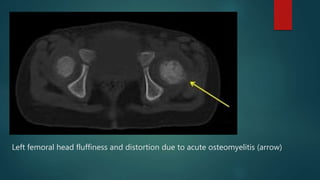

๏ต CT

๏ต Used for infection in bones that are difficult to visualize on

plain radiographs and bone scans: sternum, vertebrae,

pelvic bones, and calcaneus

๏ต Appears as rarefaction or lucent areas, on the CT scan

images

๏ต Gas may also be visible in bony abscess cavities

๏ต Limitation: disease must be present for > 1 week

Left femoral head fluffiness and distortion due to acute osteomyelitis (arrow)